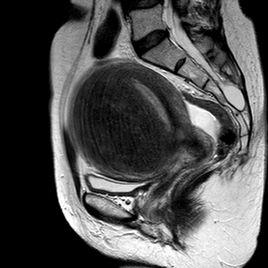

所謂子宮肌腺瘤(adenomyoma)是子宮腺肌症(adenomyosis)的一種表現,在臨床上醫師仍是以子宮腺肌症為診斷病名,較少用子宮肌腺瘤當診斷病名。有些婦女合併有經血過多、性交疼痛及不孕等問題。然而約有一半的病人是無症狀的,因為其他疾病切除子宮後,病理檢查意外發現有子宮腺肌症。內診可以發現子宮瀰漫性肥大,通常呈球狀,但很少大小超過妊娠12周的標準。月經期間子宮會腫大,內診時子宮會有壓痛,月經終了時稍微會縮小,並且壓痛會消失。超音波檢查可以發現整個子宮變大,子宮壁肥厚尤其是後壁,同時伴有超音波回音增強之特性。如果肌層肥厚集成一團呈強回音波特性的瘤狀物,一般就稱之為子宮肌腺瘤。最近也有人利用立體能量超音波來顯示子宮肌層血流變化作診斷。此外,子宮腺肌症患者的腫瘤指數CA-125有時也會升高,可以做為診斷之參考。然而真正要確定診斷仍要靠手術切除子宮或經腹腔鏡做子宮切片後,送病理切片檢查才能確定。

瀰漫型常見,子宮多呈均勻性增大,一般不超過12周妊娠子宮大小。子宮內病灶一般為瀰漫型生長,但後壁更明顯,故後壁常較前壁厚。病灶處肌層明顯增厚變硬,粗厚的肌纖維內常見黃褐色或藍色小囊腔,腔內為咖啡色稀薄液體。

局限型指異位子宮內膜在局部肌層中生長形成腫塊,又稱為子宮腺肌瘤(adenomyo—ma),但它不同於肌瘤,無假包膜,與周圍的肌層無明顯分界,因而難以將其自肌層剔出。鏡檢肌層內有呈島狀分布的子宮內膜腺體與間質,由於它們多來源於基底層內膜,對卵巢激素尤其是孕激素不敏感,故常處於增生期,但局部區域可有分泌期改變。子宮腺肌病 (adenomyosis),是由子宮內膜侵入子宮肌層引起的一種良性病變。病理上見子宮肌層肥厚,肌壁間有呈島狀分布的子宮內膜腺體與間質,伴平滑肌纖維增生。